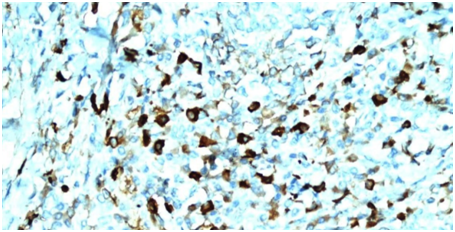

Endosonography showed a heterogeneous and hypoechoic nodular lesion of 15mm in the head of the pancreas. It was poorly delimited and had irregular edges. Ultrasound elastography revealed an indurated lesion and an area where the dilation of the pancreatic duct suddenly narrowed (Figure 3). Fine needle aspiration was performed and findings of the cytological and cell block study indicated an adenocarcinoma. The case was consulted with the surgical team and a pancreatoduodenectomy was performed without incidents. Biopsies demonstrated glandular atrophy and lymphocyte plasmocytic infiltrate (Figure 4). Immunotyping evidenced IgG4 presence in the cytoplasm of plasma cells, with an IgG4/IgG ratio greater than 40% (Figure 5). Finally, a focal autoimmune pancreatitis was diagnosed.

Figure 5 Immunotyping: IgG4 (+).